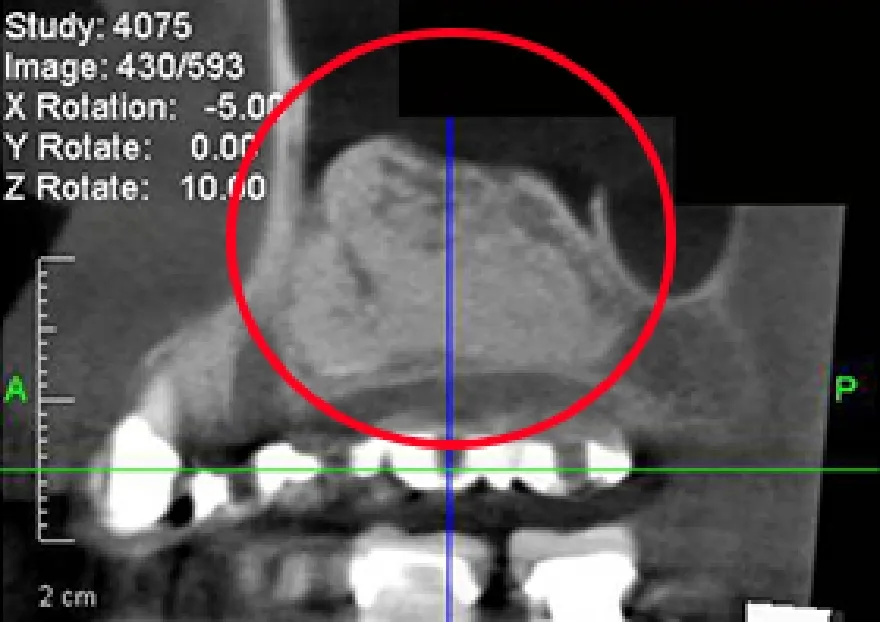

• 上顎の骨がほとんど無い状態です。

• サイナスリフトという骨再生手術で、十分な骨が出来ているのが分かります